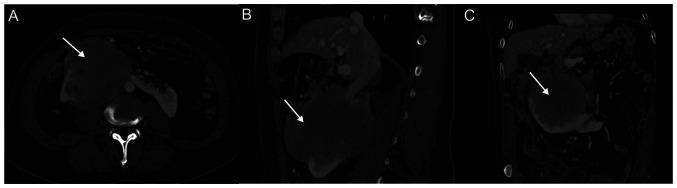

马蹄肾(HSK)是最常见的肾脏融合异常。它通常由下极跨越中线的肾脏融合组成,发生于胚胎发育过程中。马蹄肾发生恶性肿瘤的几率可能比正常肾脏高3至4倍。一名69岁男性,患有马蹄肾伴巨大右肾肿瘤及单个同侧腋窝淋巴结病,接受了右腋窝淋巴结病的完整切除及超声引导下右肾扩张性病变的经皮活检。最终诊断为马蹄肾及右腋窝均为非霍奇金B细胞淋巴瘤。我们报告该病例,以提高医生对正确临床评估和诊断检查重要性的认识,从而避免对患有这种肾脏异常的患者进行不易且有并发症的手术。原发性肾淋巴瘤也应被纳入马蹄肾可能的肿瘤之中。当影像学检查获得非典型结果且其结果会影响临床决策时,应始终建议进行肾活检。在本病例中,进行了活检,从而避免了肾切除术并迅速开始了特定的药物治疗。